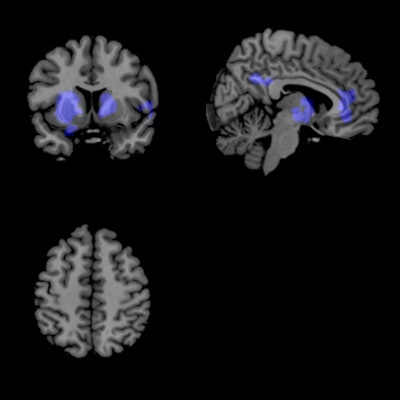

Functional MR images for patients who took the placebo pill and were off the L-DOPA medication indicated a large increase in oscillatory activity in the basal ganglia that spread to other regions of the brain like a ripple effect. When patients were given L-DOPA, their oscillatory brain activity was suppressed, and the brain essentially quieted down.

| Functional MR images of patients who were given placebo pills and were off medication show areas of increased connectivity (red); fMR images of patients who received L-DOPA to suppress brain activity show fewer areas of connectivity (blue). Images courtesy of Rachael Seidler, PhD. |